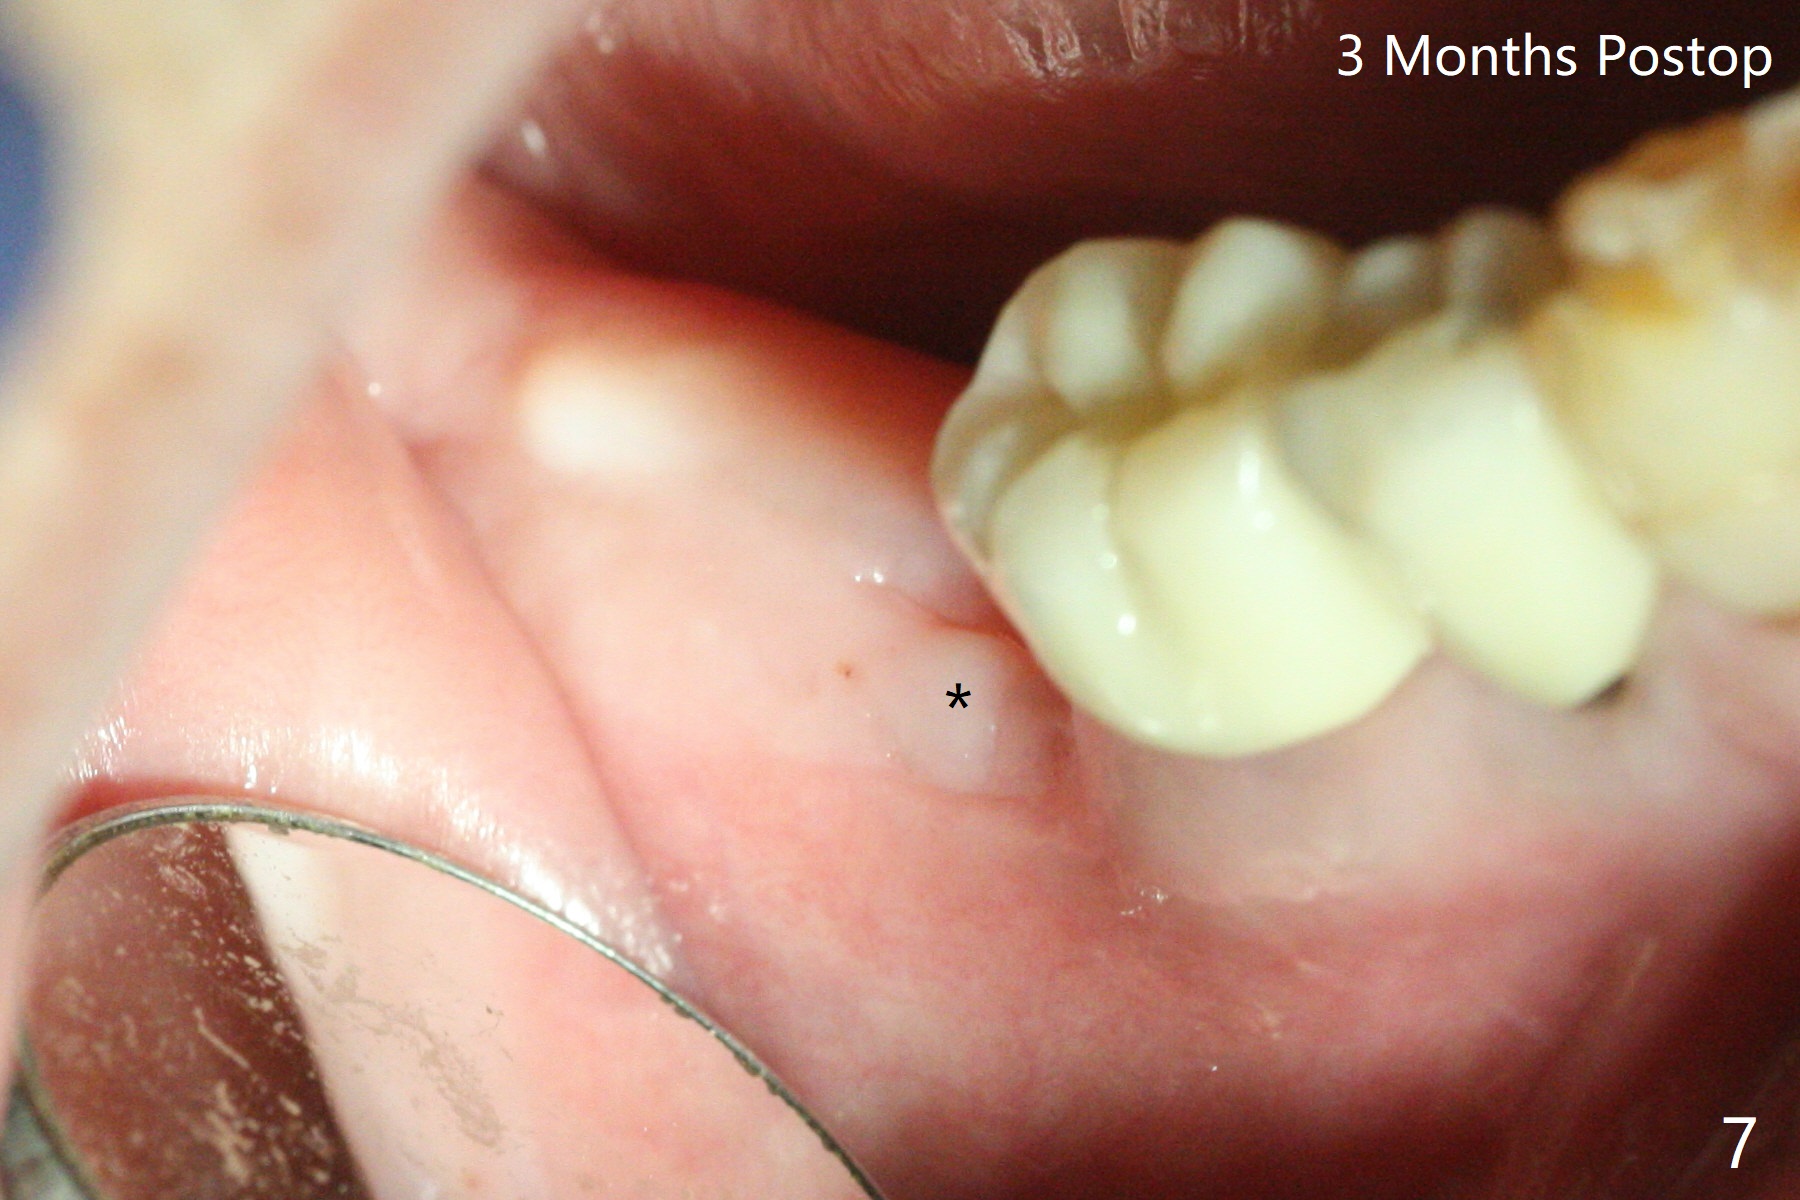

A 88-year-old man returns with pain and swelling (Fig.1), one year after diagnosis of #31 mesial root fracture. After discussion, the tooth is extracted with socket preservation (Vanilla graft mixed with Osteogen, covered with Osteogen plug and Collagen plug, Fig.2,3). The buccal crest is much lower than the lingual one. The socket opening reduces with resolution of 4-0 Chromic gut suture 1 week postop (Fig.4). The wound is wider with foul odor 2 weeks postop (data not shown). The socket and ridge shrink with loss of the bone graft 3 weeks postop (Fig.5). The bone volume reduces with buccal plate collapse 3 months postop (Fig.6,7). Immediate implant and provisional should be able to help restore the lost buccal plate. The buccal plate remains concave 5 months postop (Fig.8,9). The coronal section shows that there is space (Fig.10 *) buccal to the graft (G). A 2.0 mm pilot drill is used to create an initial osteotomy through the graft zone and in the beginning of the native bone (Fig.11,12). Use bone expanders (Fig.13 E) to push (arrowheads) and condense the graft bone and close the buccal gap. The apical portion of the osteotomy requires regular drills (Fig.14 D).